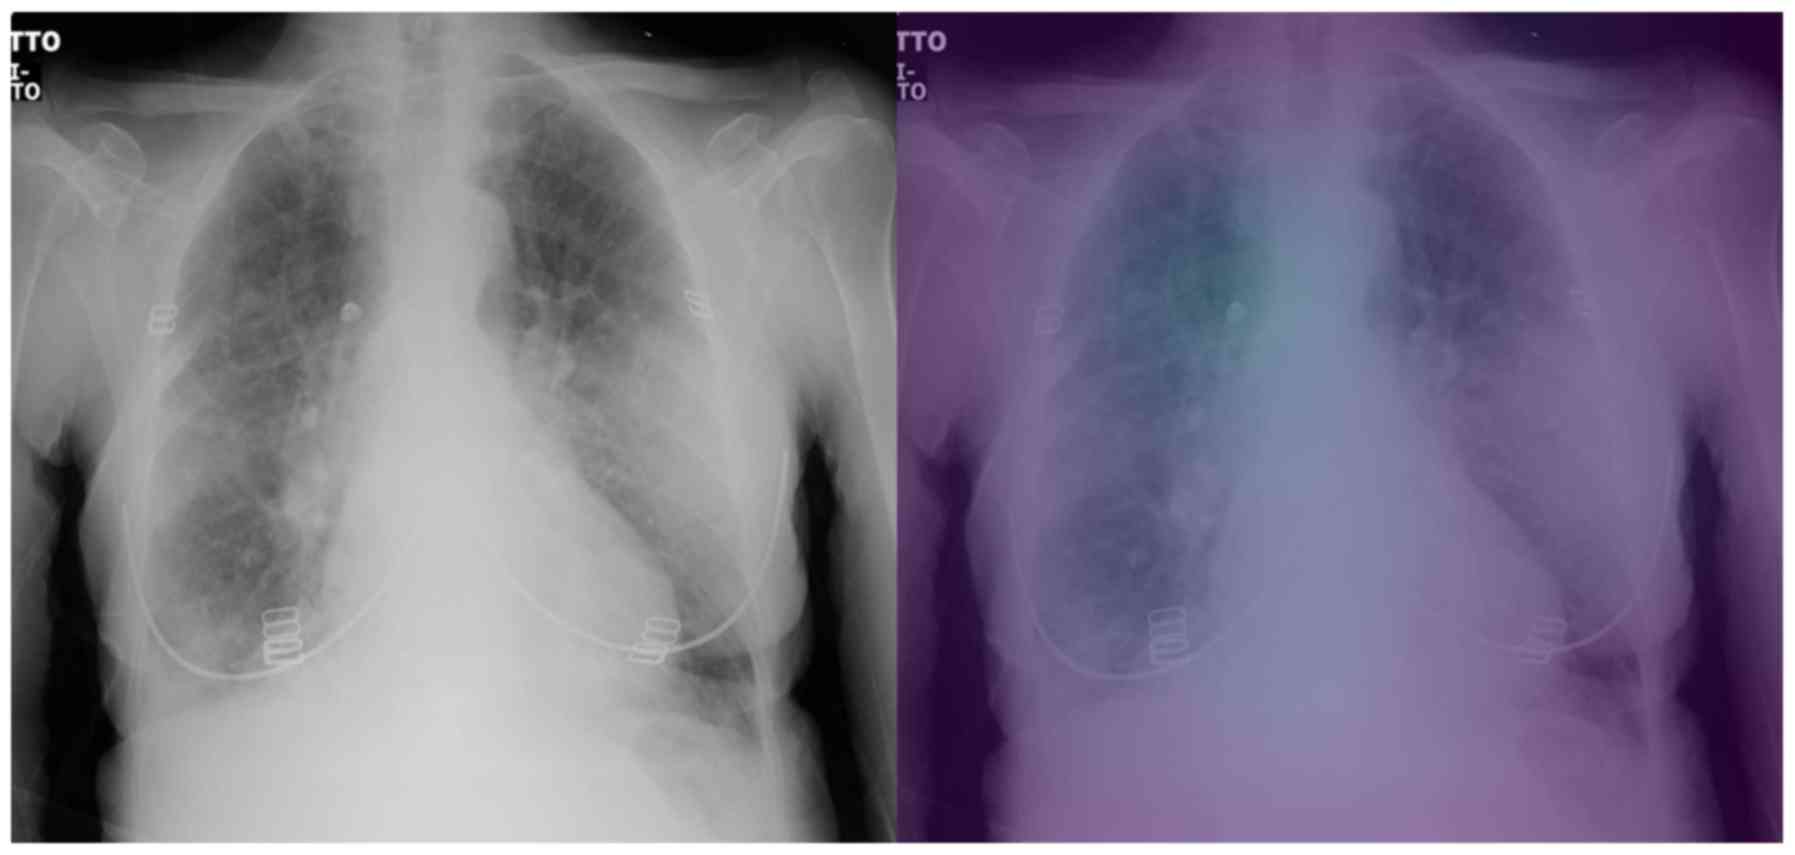

Interpretable artificial intelligence framework for COVID‑19 screening on chest X‑rays

COVID-19 has led to an unprecedented healthcare crisis with millions of infected people across the globe often pushing infrastructures, healthcare workers and entire economies beyond their limits. The scarcity of testing kits, even in developed countries, has led to extensive research efforts towards alternative solutions with high sensitivity. Chest radiological imaging paired with artificial intelligence (AI) can offer significant advantages in diagnosis of novel coronavirus infected patients. To this end, transfer learning techniques are used for overcoming the limitations emanating from the lack of relevant big datasets, enabling specialized models to converge on limited data, as in the case of X‑rays of COVID‑19 patients. In this study, we present an interpretable AI framework assessed by expert radiologists on the basis on how well the attention maps focus on the diagnostically‑relevant image regions. The proposed transfer learning methodology achieves an overall area under the curve of 1 for a binary classification problem across a 5‑fold training/testing dataset.